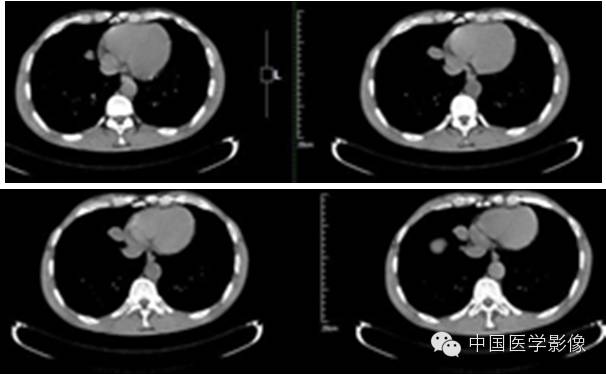

病例2【病史】

患者男,47岁。

患者因“查体发现右纵膈区占位2周”入院。患者无胸痛、胸闷,无发热、盗汗,无咳嗽、咳痰。CT示:右心膈角处新生物,考虑来自叶间裂的炎性假瘤可能性大,不除外其他肿瘤可能。

专科查体:(-)

入院诊断:右下纵膈占位:心包囊肿?炎性假瘤?

【影像资料】

平扫